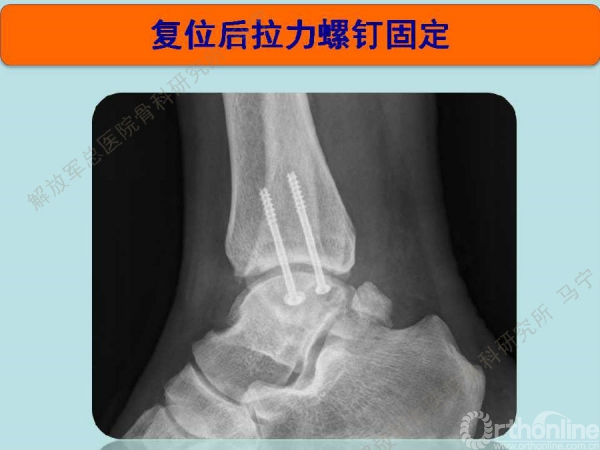

术后5天复查,复位的位置良好。

术后5天复查,复位的位置良好,完全解剖复位。